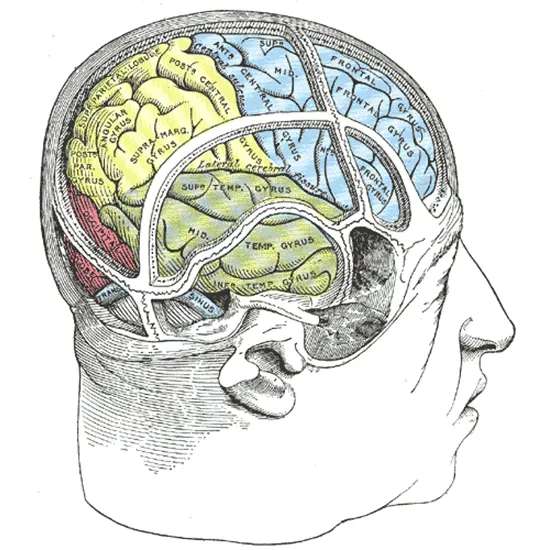

Although damage to the parietal lobe or other parts of the brain can also cause the illness, right hemisphere damage is the most common cause.

The parietal lobe, which is situated close to the top and rear of the brain, is essential for combining sensory data from various body regions and the surroundings. Damage to the right hemisphere of the brain or the parietal lobe might impair judgement.